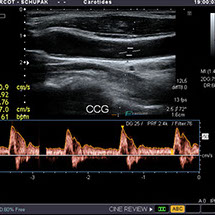

Echographie - Doppler

C'est une technique complémentaire à l'échographie utilisant une propriété physique des ultrasons dont la fréquence émise est modifiée lorsqu'il est réfléchi par un corps en mouvement (les globules rouges dans ce cas particulier).

Le doppler (ou écho-doppler) est destiné à l'étude des vaisseaux (artères et veines).

Il permet un encodage (une "colorisation") des structures vasculaires contenant des globules circulants (Doppler couleur ou " Energy ") et une étude des flux circulants (Doppler pulsé) permettant de détecter des rétrécissements voire des obstructions complètes du vaisseau (veine ou artère).

Lors de l'examen, vous pourrez alors voir sur l'écran de contrôle des structures colorées (le plus souvent en bleu et en rouge) et entendre des bruits (sourd et continu pour les veines, plus aigu et modulés selon les pulsations du coeur pour les artères).